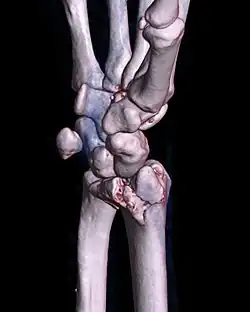

| A palmar Barton's fracture of the right wrist, as shown on a 3D-rendered CT scan | |

A Barton's fracture is a type of wrist injury where there is a broken bone associated with a dislocated bone in the wrist, typically occurring after falling on top of a bent wrist.[1] It is an intra-articular fracture of the distal radius with dislocation of the radiocarpal joint.[2]

There exist two types of Barton's fracture – dorsal[3] and palmar, the latter being more common. The Barton's fracture is caused by a fall on an extended and pronated wrist increasing carpal compression force on the dorsal rim. Intra-articular component distinguishes this fracture from a Smith's or a Colles' fracture. Treatment of this fracture is usually done by open reduction and internal fixation with a plate and screws, but occasionally the fracture can be treated conservatively.[4]